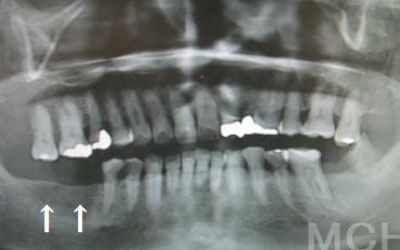

CTでは、骨や歯の状態を3Dで確認でき、正確な距離の測定も行えます。

骨の厚さや傾き、神経の位置などを事前にしっかりと測定することで、安全にインプラントを行うことができます。